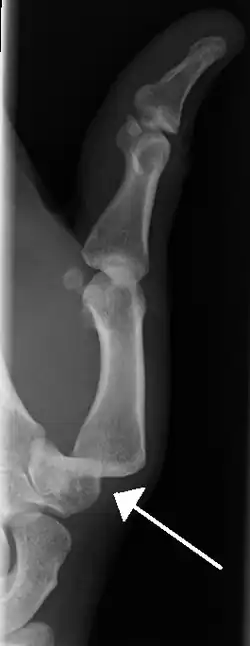

Dislocation of the left index finger -

Radiograph of right fifth phalanx bone dislocation -

Radiograph of left index finger dislocation